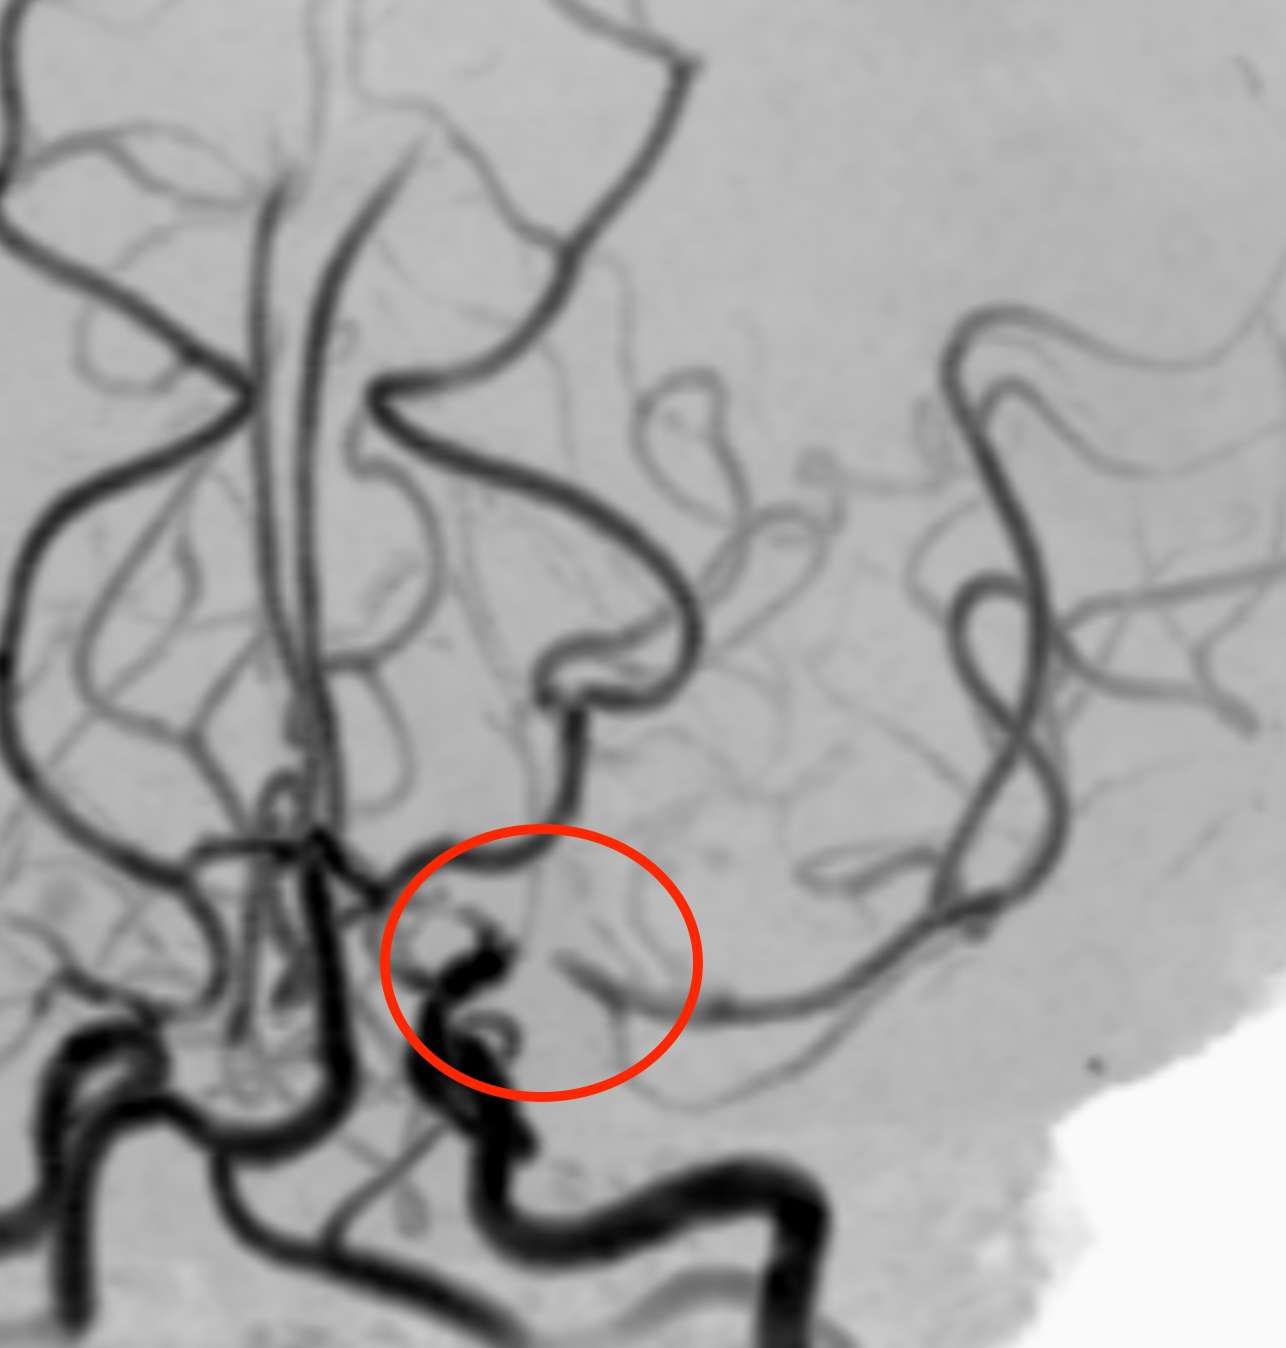

頭部MRA検査で血管を見ました。

片頭痛と脳梗塞

左の中大脳動脈という血管に細い部分がありました。つまり、可逆性脳血管攣縮症候群を生じ、血流が悪化して脳梗塞を起こしたものと考えられました。